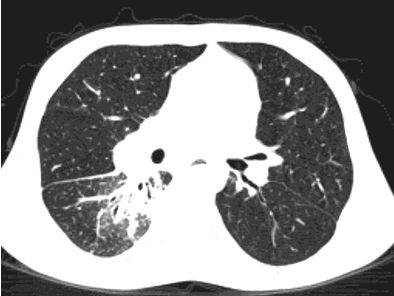

Чтобы человек несведущий смог разобраться в результатах КТ, следует знать о нюансах чтения снимков. Рассмотрим самые актуальные:

- Очаговые образования представляют собой участки белого цвета на черном фоне (на снимке-негативе). В реальности пораженная область, скорее всего, имеет более темный цвет, чем здоровые ткани легкого.

- Если врач заметит на снимке участки кальцинирования или обызвествления (капсул, пропитанных солями кальция) вокруг очага, это может быть признаком доброкачественности образования. Кальцинаты по цвету похожи на кости скелета, видимые на этом снимке. Такие явления часто обнаруживаются после затяжных простудных заболеваний, бронхитов или уже излечененного туберкулеза и представляют собой некий шрам на легких. Пациента с образованием, на котором заметны признаки кальцината, пульмонологи обычно просят раз в полгода делать контрольные снимки.

- В случае, когда образование представляет собой так называемое «облачко» или очаг по типу «матового стекла», требуется более предметное обследование. Внешне оно выглядит как затуманенная область с размытыми границами. В ряде стран пациентам с такими образованиями сразу рекомендуется операция, даже если оно не растет. Уже доказано, что в 80% случаев такие очаги являются предраковым состоянием легких. Альтернатива немедленной операции — постоянное наблюдение с контрольными снимками раз в полгода-год.

Очаговые изменения

Очаговые изменения в лёгких могут быть разного размера. Очаги мелкого диаметра 1-10 мм выявляются при различных диффузных патологиях лёгочной ткани. Очаги с высокой плотностью и довольно чётки краями в основном наблюдаются в интерстиции лёгкого. Различные очаги низкой плотности, напоминающие матовое стекло, с нечёткими контурами возникают при патологических изменениях в респираторных отделах дыхательных органов.

Нужно учитывать, что плотность и размер очагов имеет слабое диагностическое значение. Для постановки диагноза более важным может быть распределение патологических процессов в лёгочной ткани: